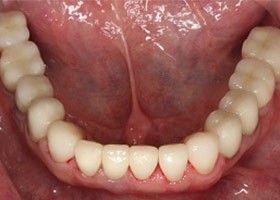

治療後

proimages/Case/dentalimplant/10/02/after01.jpg

proimages/Case/dentalimplant/10/02/after02.jpg

proimages/Case/dentalimplant/10/02/after03.jpg

proimages/Case/dentalimplant/10/02/after04.jpg